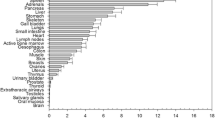

The study group consisted of 27 male and 13 female patients with a mean ± SD age of 68 ± 12 years and mean ± SD body mass index (BMI) of 26.7 ± 5.1 kg/m2. Table 2 gives an overview of the average organ doses for the CBCT run and standard error of the mean as well as associated tissue weighting factors [14]. The radiation dose was highest in the kidneys, spleen, adrenals, pancreas, and liver for upper abdominal CBCT and by ovaries, uterus, colon, small intestine, urinary bladder, and active bone marrow for lower abdominal CBCT. Table 3 provides summarized results of CBCT radiation exposure estimation. ED of the CBCT run was estimated to be in the range of 1.1–7.4 mSv. Mean ED for upper abdominal CBCT was 4.9 mSv (95 % confidence interval [CI] 4.3–5.4 mSv) and mean ED for lower abdominal CBCT was 3.5 mSv (95 % CI 3.0–4.1 mSv); differences between upper and lower abdominal X-ray field location were statistically significant (p = 0.003).

Calculated risk of CBCT exposure-induced death based on organ doses for various cancer types is shown in Fig. 4 as a function of age and body weight. For example, for a 60-year-old female patient with a body weight of 78 kg, the stochastic risk for exposure-related cancer death was 0.0182 % for upper abdominal CBCT and 0.0147 % for lower abdominal CBCT, respectively. Calculated maximum risk for lifetime exposure induced death was 0.033 %.